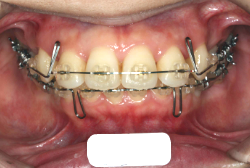

牽引(埋伏犬歯を牽引した症例)

「乳歯が生え替わらない」という主訴で来院したケースです。 診断の結果、「左上永久犬歯が第一小臼歯後方上部に埋伏しているため、左上乳犬歯が晩期残存している症例」と判明しました。

このような症状の場合は、手術で埋伏している永久歯に金具を取り付け、矯正装置で牽引する必要があります。同時に凸凹の解消と前突した前歯を内側に入れるために上下左右の小臼歯を抜歯させて頂くことといたしました。

この方の場合は、マルチブラケット装置にて治療を開始し、治療期間2年3ヶ月で終了しました。犬歯の牽引距離が非常に大きかったため当院の平均治療期間よりも大幅に期間がかかりましたが、埋伏犬歯を完全に正しい位置まで誘導することができました。同時に 前歯の前突と配列の凸凹も解消しました。